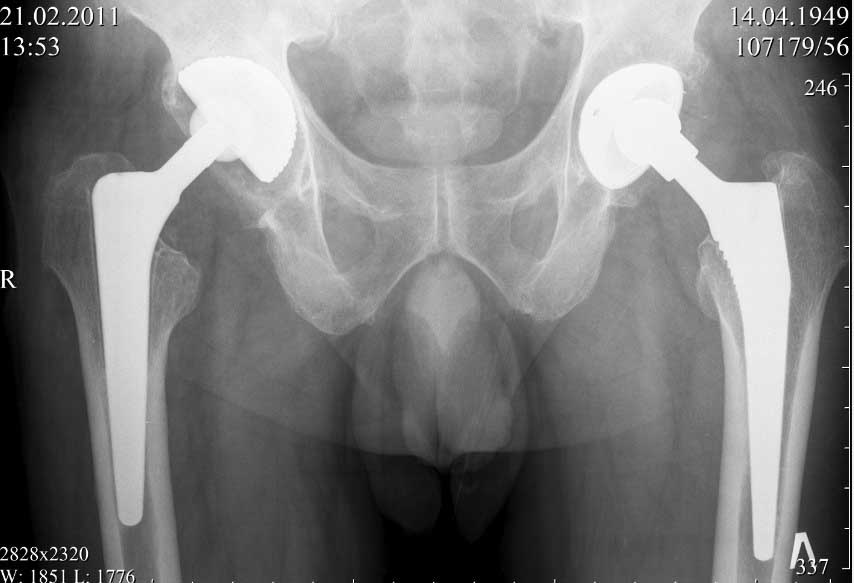

далее снимок у меня на приеме

На заключительных снимках явная нестабильность чашки и вероятная ножки, возможно на повторный прием придет не столь радостный (пессимистический прогноз) надеюсь, что все будет по-другому

Нет вы не поняли! Вы поспешили с выводом! Я не смог выслать окончательный, послеоперационный снимок, по техническим причинам. Я это сделал позже, что Вы и видите ниже! Извините, если я Вас запутал!

С последним, третьим снимком он ко мне и обратился, после чего он был и прооперирован на правом тазобедренном суставе!